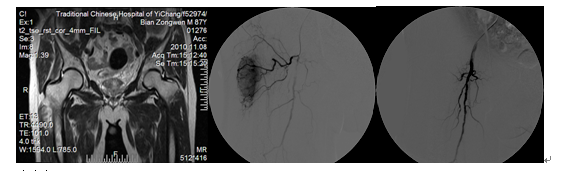

典型病例一、男、87岁,2010年因肺癌右侧大腿转移剧烈疼痛,磁共振检查右下肢软组织肿块,行微创介入栓塞术后第二天患者疼痛消失。